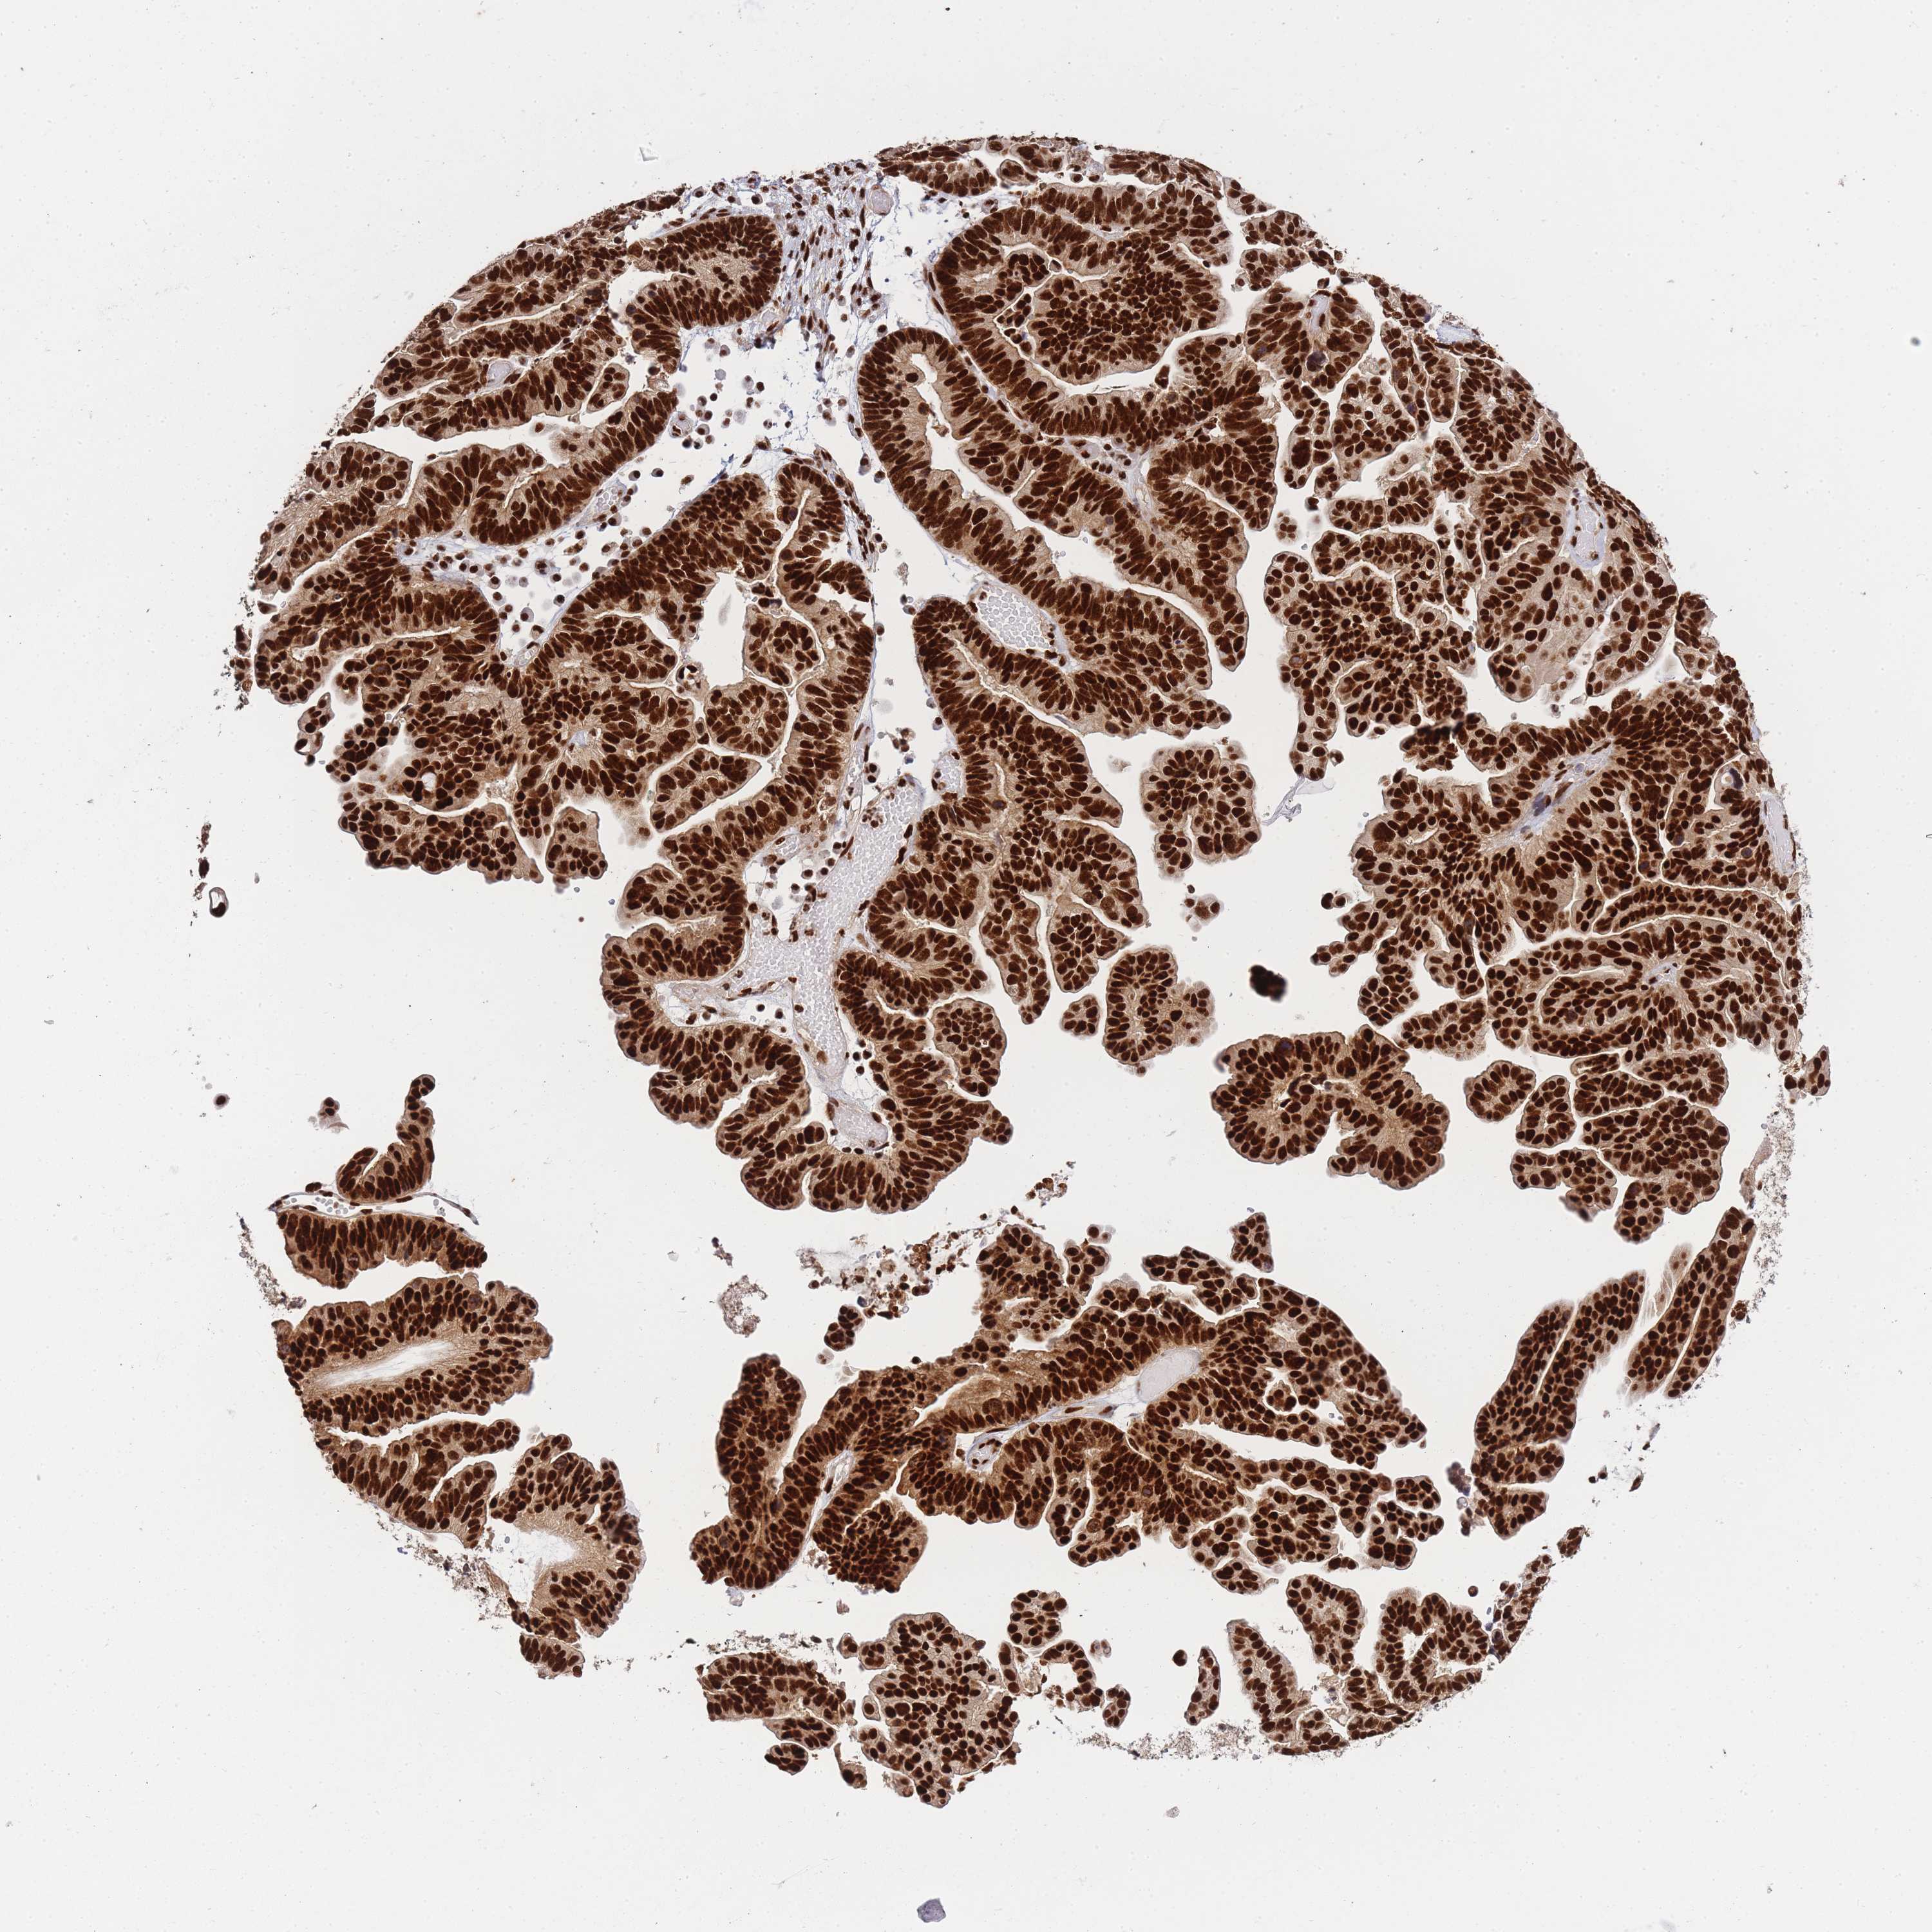

OVARIAN CANCER - Protein expressioni

A mouse-over function shows sample information and annotation data. Click on an image to view it in a full screen mode. Samples can be filtered based on level of antibody staining by selecting one or several of the following categories: high, medium, low and not detected. The assay and annotation is described here.

Note that samples used for immunohistochemistry by the Human Protein Atlas do not correspond to samples in the TCGA dataset.

Antibody stainingi

Antibody staining in the annotated cell types in the current human tissue is reported as not detected, low, medium, or high, based on conventional immunohistochemistry profiling in selected tissues. This score is based on the combination of the staining intensity and fraction of stained cells.

Each image is clickable and will lead to virtual microscopy that enables deeper exploration of all samples and also displays staining intensity scores, fraction scores and subcellular localization as well as patient and tissue information for each sample.

Antibody HPA035174

Antibody CAB005167

Staining

High

Cystadenocarcinoma, serous, NOS